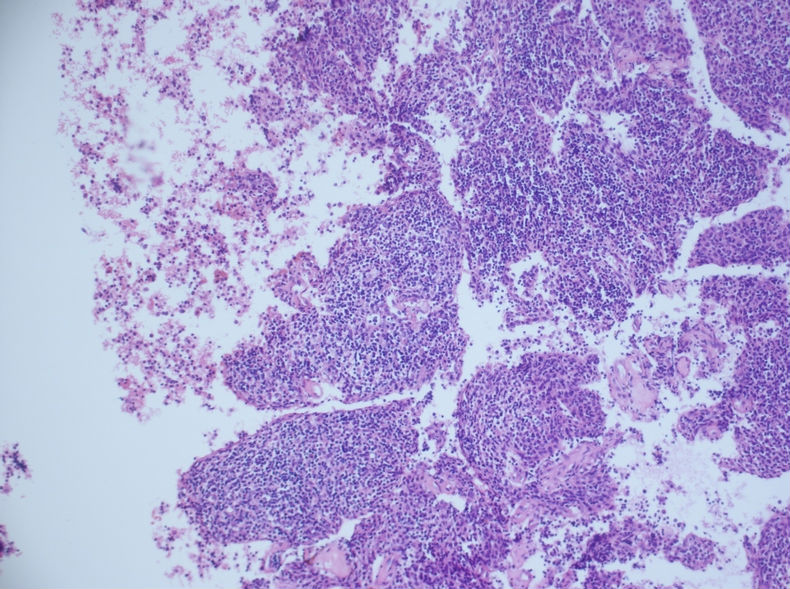

发现左侧胸壁肋间肿块1月,约3.5×4 。病例分享——男性,55岁,左胸壁肋间肿块图1

术后病理示:胸腺瘤(B3型为主)

的确这例涂片诊断非常困难,我刚看到涂片的时候,也是一团雾水,我看到淋巴细胞及组织细胞样细胞两种成分。

当时考虑:1、肉芽肿性炎,2、转移性鼻咽部的非角化性未分化癌、3、淋巴结增生、4、转移性胸腺瘤,5、软组织肿瘤6、……

反正良恶性我分不清。

细胞腊块图片如下:

根据腊块及免疫组化结果,我诊断了

(左胸壁)转移性胸腺瘤(B2型)

建议检查纵隔。

随访,纵隔发现一3.5×3cm肿块,术后病理示:胸腺瘤(B3型为主)

肋间肿块切除的标本有的,形态和细胞腊块一致,属于胸腺瘤B2+B3型。